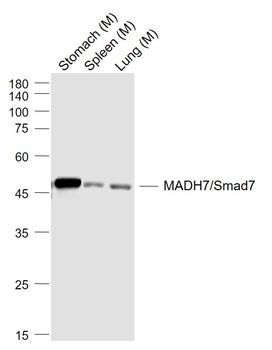

100 μl, 200 μl, 50 μlSMAD7 Rabbit Polyclonal Antibody [orb500819]

FC, ICC, IF, IHC-Fr, IHC-P, WB

Bovine, Porcine

Human, Mouse, Rat

Rabbit

Polyclonal

Unconjugated

100 μl, 200 μl, 50 μlPhospho-Smad3 (Ser213) Rabbit Polyclonal Antibody [orb106193]